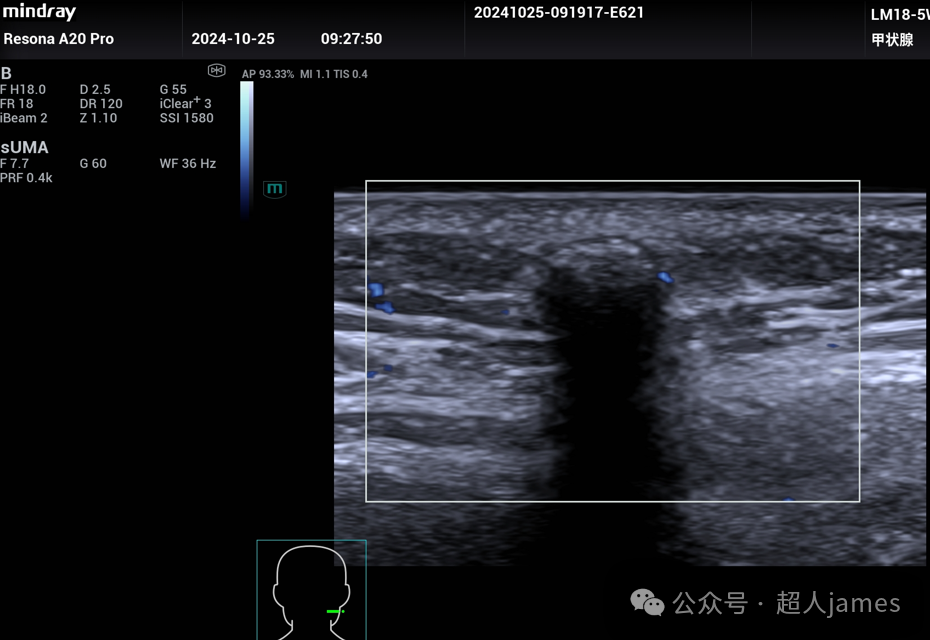

超声表现多样,可以表现为实质片状钙化型、点状钙化灶型、无钙化型、完全钙化型等,边界清晰,后方衰减。利用UMA超微血流成像显示:实质区域可以探及血流信号,这一点是与皮脂腺囊肿、表皮样囊肿的重要鉴别点。